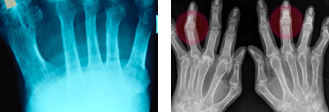

그러나, 급성으로 발생하거나 소수의 관절에만 생기는 경우가 있기 때문에 방사선 촬영 및 류마티스 인자와 같은 피검사도 진단하는데 도움이 됩니다. 방사선 촬영상 초기에는 정상일 수 있지만, 때로는 뼈를 파먹은 소견(골미란)을 볼 수 있고 진행하면 관절이 파괴되어 뼈끼리 붙은 소견(강직)을 볼 수 있습니다. 즉, 방사선 검사는 질환의 진행 및 손상 정도를 파악하는데 중요합니다.